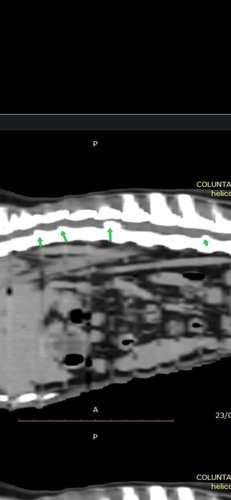

Kiara Helena, é uma cadela sem raça definida, de 5 anos. No início de abril/2023 precisou realizar uma cirurgia de obstrução de intestino com urgência. Fez exames, internações e uso de medicamentos. O pós operatório foi muito complicado, pois ela começou a sentir outras dores, das quais o veterinário não chegava a conclusão do que seria. Assim foram mais exames, medicamentos e tratamentos. Vendo que ela só piorava e ainda não sabiamos o que ela tinha, fomos para outra clínica, e foram mais exames até o diagnóstico de hérnia na coluna. Começamos assim um novo tratamento, sendo mais gastos. Após 2 semanas, na qual ela teve uma leve melhora, ela voltou a piorar. Precisou ser internada, fazer vários exames que entre eles, foi necessária uma tomografia. E assim, possivelmente (ainda não temos o resultado do exame) vai ser necessária a cirurgia.